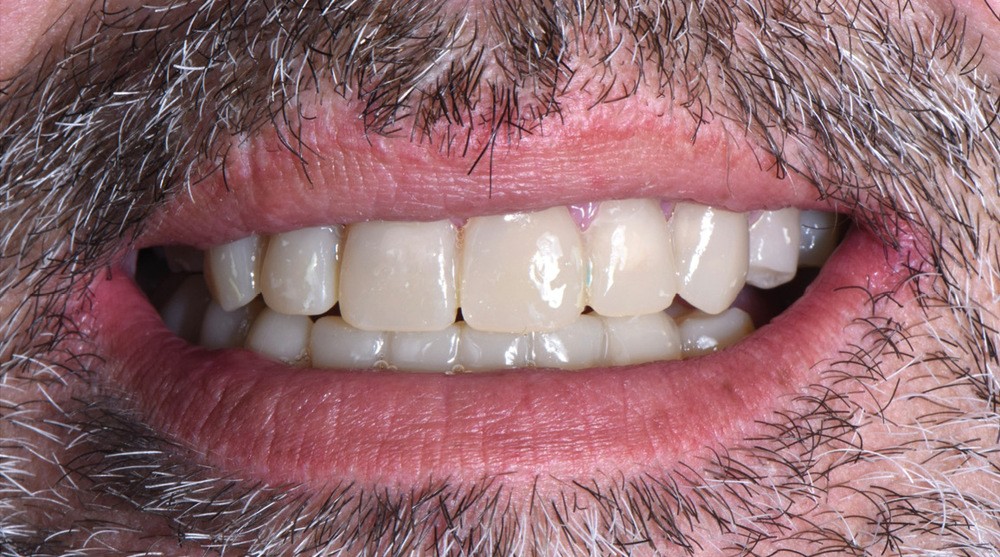

Au vu du contexte para-fonctionnel et de l’étendue de la perte tissulaire, des coiffes périphériques minimalement invasives ont été choisies afin de restaurer l’esthétique et la fonction. Actuellement, aucun consensus n’est fait sur le choix du matériau d’infrastructure à privilégier. Les matériaux hybrides usinables présentent des propriétés mécaniques, physiques et biologiques intéressantes en contexte d’usure sévère (e.g., module d’élasticité, résistance à la propagation de fêlures, facilité de réintervention). Une réhabilitation globale avec remontée de dimension verticale d’occlusion (DVO) par l’intermédiaire de coiffes composites renforcés en nano-céramiques est décrite.